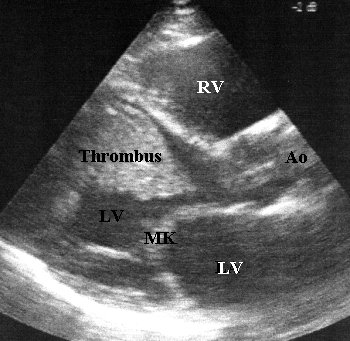

Echokardiographie

- Hypokinesie aller Herzwände

- Mitralinsuffizienz II°, Trikuspidalinsuffizienz

II°

- im linken Ventrikel stellt sich

ein die Kammer nahezu ausfüllender Thrombus dar, teilweise organisiert

(4x4cm) mit frei flottierendem Anteil (2x4cm), der Berührung mit der

Aortenklappe aufnimmt

- im rechten Ventrikel 2x2cm, organisierter

Thrombus im Bereich der Herzspitze